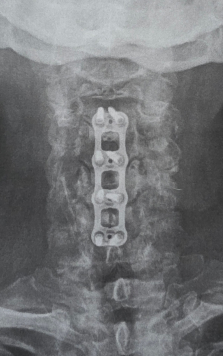

The time has come to take a break from the shop for a few weeks as I have neck surgery coming up in a few days. The surgeon will be fusing C4, C5, C6, and C7 vertebrae in hopes of releasing encapsulated nerves so that my left shoulder can work again. For the past 2.5 months I lost use of the shoulder 100%: best way to picture it is to glue your elbow to your rib and you can only mover the lower arm anywhere it wants, kind of like a T-Rex. :-) Otherwise my arm has not been able to move forward, outward, or upward. The good news is that I have had zero pain…the only time it’s been real fun is when I lost my balance twice to my left and had no arm to stop me from falling into the wall or whatever was in my path. I pitied those objects as I’m a big lug. No other harm done, except maybe that which I hit. ***NEW PAGE: “Gift Ideas”, which are non-flute items I’ve created…I love various forms of art and photography, and I have a 2026 calendar of my wildflife photography as well as 2 different sets of five notecards from Haywood County. One is of scenic views, and the other is of wildlife. The cards are 5” x 7”, providing a good amount of space for writing longer notes. These have been only recently produced, so have not yet hit the market, so to speak. Admittedly I’m still trying to nail down the price since the price of shipping is such a bugger anymore, but I’ll post that as soon as I can find affordable mailers and have the shipping priced out. The calendar features only five critters from Haywood County, the rest from other places. The cover is one of my favorite animals of all, the Barred Owl, this one sitting quite often right by home, All pictures enlarge nicely when you click on them, so you can see more of the details. The cards have additional information on the back of each, FYI. # # # I’m doing my best to stay on top of the MOUNTAINOUS emails full of too much spam, but if you don’t hear from me in a timely manner please gently nudge me again. The amount of emails is stupid, and building constantly…I clear out up to 200 junk emails every day, and heaven forbid a skip a day or two. Eegads… Knowing me, I’ll be sneaking in to the shop even if to try and clean it up and organize things better as I convalesce. Lord knows there is almost no limit to what needs to be done down there, and I have some stunning wood I can’t wait to get cutting. On top of more Spalted Tamarind, I have some figured Cheche and a new wood that I’d never heard of, Muirapixuna. It’s very much like chocolate brown Ebony, but a totally different species, from Brazil. Stay tuned! Browse and enjoy! Email with any questions. Bob Child weatherflute@yahoo.com